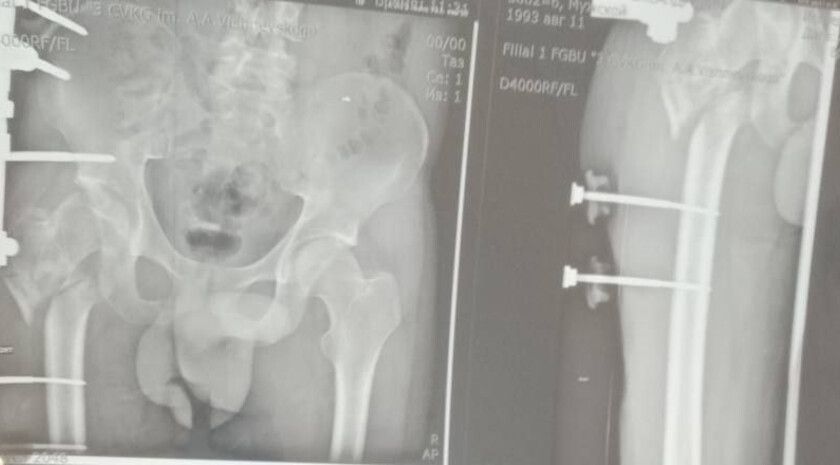

Об этом сообщила министр здравоохранения ЛНР Наталия Пащенко.Руководитель Минздрава рассказала, что борьба сержанта из ЛНР, мужчины 1993 года рождения, длилась три с половиной года. За это время он проходил лечение в десяти госпиталях, в том числе в...

Уникальная операция в Луганской республиканской клинической больнице вернула ветерану специальной военной операции (СВО) возможность ходить без хромоты. Об этом сообщила министр здравоохранения ЛНР Наталия Пащенко. Руководитель Минздрава...

Об этом сообщила министр здравоохранения ЛНР Наталия Пащенко в своем телеграм-канале.Боец ушел на фронт 25 февраля 2022 года, прошел через горнило Херсонщины, а тяжелое ранение получил 28 августа.«Из-за обширных повреждений и многократных операций...